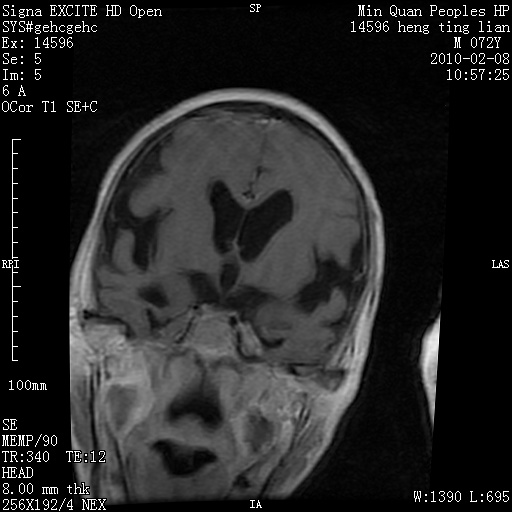

m,72,头疼,头晕两年,伴视力模糊三月,饮食呛咳两天。pe:颈部抵抗,左眼突出,左眼瞳孔约3mm,对光反射消失,双眼失明,伸舌困难,双肺呼吸音粗,心率110次/分,左上肢肌力i级,左下肢屈曲,肌张力高。现有08年2月19mri平扫及10年2月8日mri增强请会诊。ct病灶呈低密度伴散在点、片状等密度区,无明确钙化(无ct片资料可供上传)。[

脑外肿瘤,囊实性,环状不规则强化,内听道扩大,考虑神经源性肿瘤

左侧桥小脑区占位伴梗阻性脑积水----考虑 1神经鞘瘤 2室管膜瘤。

左侧桥小脑区神经鞘瘤伴梗阻性脑积水。

脑外肿瘤,病灶呈匍匐蔓延,表皮样囊肿可能性大。